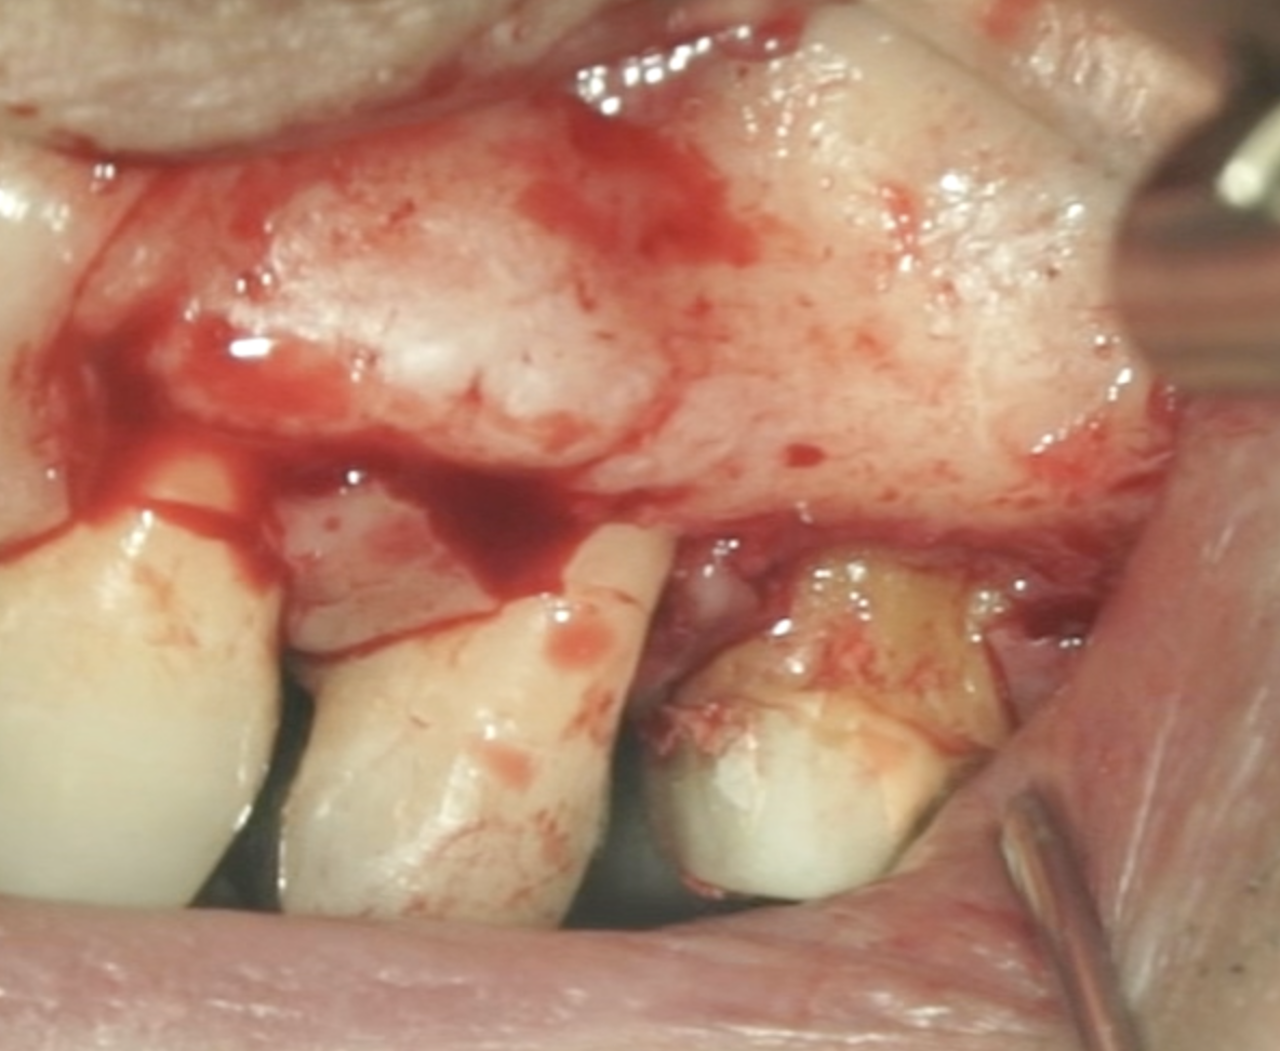

#14 MB,DB Apicoectomy→Intentional Replantation(2024.6.21)

そもそもは頬側の皮質骨はあったのだが、

抜歯時にMB,DBを短くしておこうと切断して抜歯をしようとするが…

それでも抜けない…

抜歯作業中に、私は気づかないうちにApico-marginal deffectを人為的に作成してしまっていたようだ。